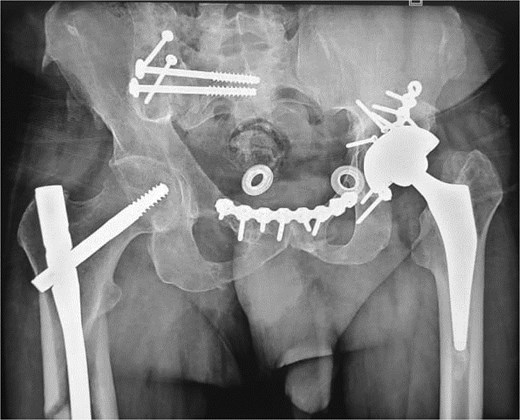

This was a 42-year-old male patient with no previous medical history who was admitted to the intensive care unit for treatment of polytrauma: severe chest trauma and pelvic trauma. During his stay in intensive care, the patient developed a pulmonary infection complicated by septicemia, requiring prolonged antibiotic therapy and thereby contraindicating any internal surgical fixation. After hemodynamic and respiratory stabilization, he was transferred to our department 40 days after the trauma with the following injuries: an unstable pelvic ring fracture classified as Tile-AO B1-2 [4]: disjunction of the pubic symphysis, disjunction of the right sacroiliac joint, and an ipsilateral crescent fracture classified as Kumar-Day 2 [5], along with a transverse–posterior wall fracture of the left acetabulum associated with a posterior dislocation of the hip, which was initially reduced but remained unstable. Fixation was performed using a Hoffmann II external fixator applied to the iliac crests with poor reduction (Fig. 1). He presented with complete weakness of the left foot dorsiflexors, with preserved sensation and no urogenital or abdominal complications. ORIF was performed in two stages, 5 days apart. The first stage consisted of performing the first two windows of the ilioinguinal approach: the lateral window to access the sacroiliac joint and the middle window to access the lower part of the sacroiliac joint and remove the osteofibrous callus. A Pfannenstiel approach was used to remove the callus at the pubic symphysis and fix it with a plate. The patient was then placed in the prone position and a posterior approach to the right sacroiliac joint was performed to carry out the same procedures on the posterior part of this joint and to perform fixation using ilioiliac and iliosacral screws. The second stage of the operation involved acetabular surgery. Given the chronic dislocation of the left hip, an anterior approach to the hip was performed to remove the intra-articular fibrosis facilitating the subsequent reduction of the femoral head. A Kocher-Langenbeck approach was then performed to remove the callus, reduce the femoral head and fracture, and fix it with a plate (Fig. 2). Postoperatively, the patient retained neurological deficits. At 6 months, the patient was able to walk without assistance and had a Harris Hip Score (HHS) score of 80 and Majeed score of 75 [6, 7].

Immediate postoperative X-rays. (a) Anteroposterior pelvic X-ray. (b) Inlet view of the pelvis. (c) Alar oblique view of the pelvis. (d) Obturator oblique view of the pelvis.